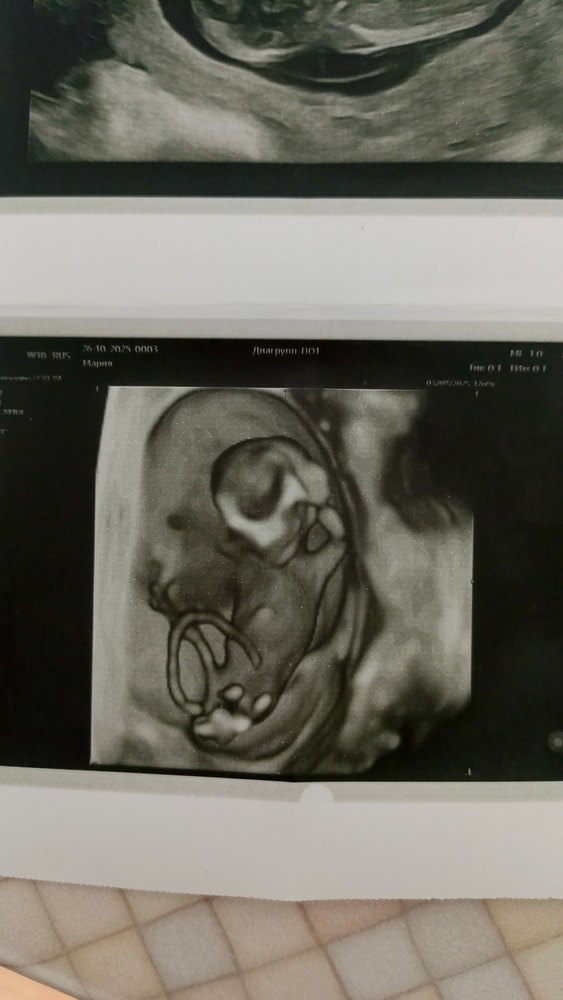

Это половой бугорок, на вашем сроке он выглядит совершенно одинаково у мальчиков и девочек. Поэтому гадать совершенно бесполезно. Пол на вашем сроке говорят только врачи, в свое время проспавшие на задней скамье лекцию по эмбриогенезу половых органов

По форме черепа девочка! Посмотрите какая миленькая черепушечка!! 🥰

На таком фото не увидеть , надо смотреть половой бугорок под наклоном … в 3 /4 д у всех на таком сроке «писюн» …

Ничего не видно, очень рано еще